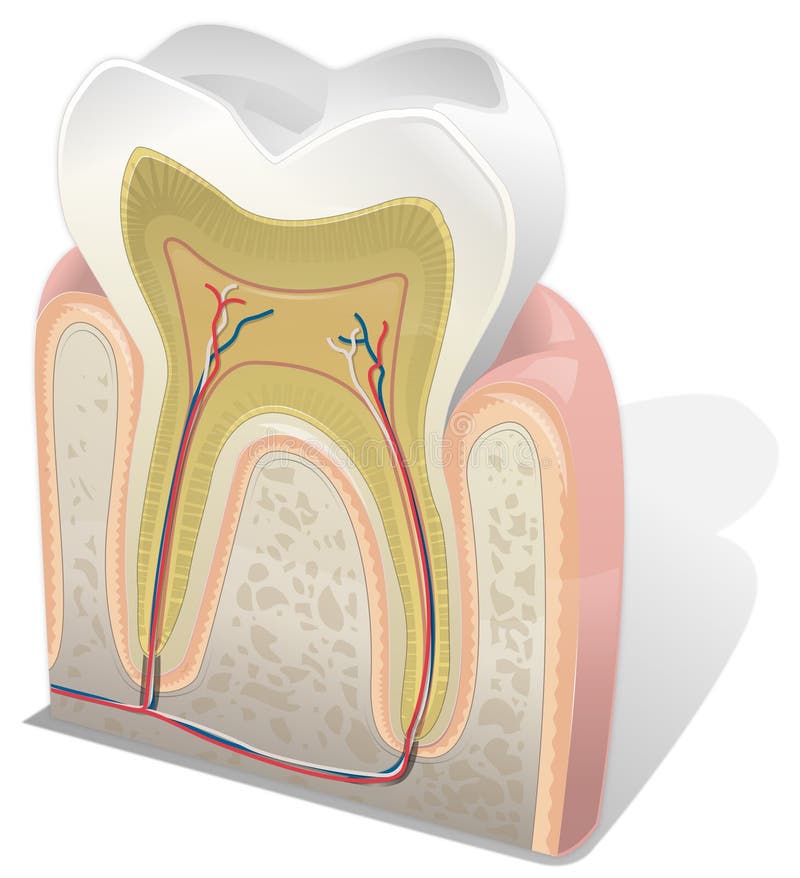

Tanden strukturerar Medicinskt diagram av strukturen av det inre tvärsnittet av tanden